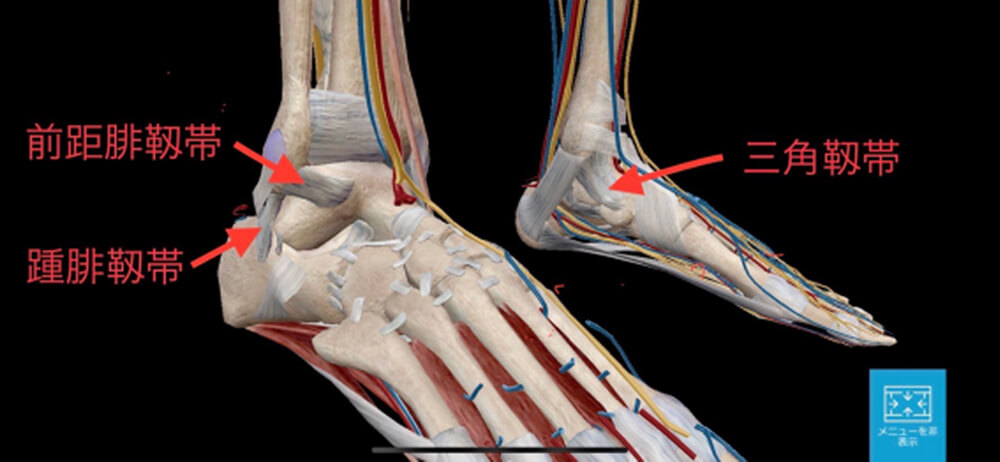

解剖

足関節には内側の三角靱帯と、外側の前距腓靱帯・踵腓靱帯があります。

足関節内がえしで受傷する外側靱帯損傷が全体の90%を占めます。

足関節